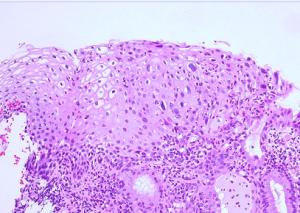

Low Grade Squamous Intraepithelial Lesion is a gynaecological medical condition that attacks a particular body part and result in outgrowths in the human body; especially in women.

The shape of a squamous cell is like a plate (just like thrombocytes in case of blood cells) and they are present in the epithelium in abundance around its edges. The Low Grade Squamous Intraepithelial Lesion usually develops in the cervix. Scientists have not yet been able to point out the exact cause of this condition but in most cases an injury to the cervix is followed by this condition. However, it does not mean that a woman will suffer with Low Grade Squamous Intraepithelial Lesion whenever she has an injury in the cervix but statistical studies show that it usually is a trigger for this condition. The lumps of skin growth start surfacing during the recovery period after sustaining the injury.

Statistical date and the observation of top physicians across the globe have however been able to point fingers at some potential causes. As stated earlier, Low Grade Squamous Intraepithelial Lesion is a gynaecological condition and it usually attacks women who have attained menopause. The average age of those who have suffered from this condition is fifty. People suffering from the AIDS-HIV virus are known to develop Low Grade Squamous Intraepithelial Lesion and the percentage of smokers suffering from the condition is also high. However, some scientists believe that infection in the human papillomavirus may be a major cause for Low Grade Squamous Intraepithelial Lesion.